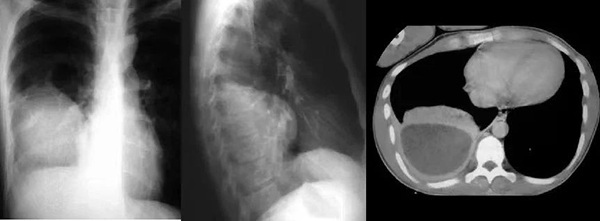

近日,一位70歲男性患者,因“反復(fù)咳喘3余年,加重1周”住院治療?;颊呷朐汉笮行夭緾T提示右側(cè)大量胸腔積液,進(jìn)一步完善胸腔彩超提示:右側(cè)包裹性胸腔積液?;颊咝貝灐舛贪Y狀明顯,偶有痰中帶血情況??垢腥局委熜Ч患选?/p>

為進(jìn)一步明確診斷、改善患者癥狀,擬行包裹性積液胸腔穿刺置管引流術(shù)。但常規(guī)胸腔穿刺引流極易造成穿刺損傷及穿刺失敗風(fēng)險(xiǎn),較以往相比因技術(shù)難度和風(fēng)險(xiǎn)高。史淑利醫(yī)生與青南支醫(yī)專家范得艷醫(yī)生綜合分析患者病情后,決定聯(lián)合超聲科為患者行床旁超聲引導(dǎo)下包裹性胸腔積液穿刺置管引流術(shù)。在手術(shù)過程中,由超聲科醫(yī)生首先對(duì)包裹性積液進(jìn)行定位,由史淑利醫(yī)生親自為患者進(jìn)行胸腔積液穿刺置管術(shù),手術(shù)順利完成。整個(gè)過程如同一場(chǎng)精細(xì)的外科手術(shù),每一個(gè)步驟都嚴(yán)謹(jǐn)而準(zhǔn)確。術(shù)后史淑利醫(yī)生向年輕醫(yī)生進(jìn)行了胸腔穿刺術(shù)和胸腔積液的教學(xué)查房,向她們講解胸腔穿刺的適應(yīng)癥、禁忌癥、注意事項(xiàng)、可能出現(xiàn)的不良反應(yīng)及處置方案,胸腔積液鑒別診斷。通過胸水結(jié)果分析,患者明確診斷“肺結(jié)核;結(jié)核性胸膜炎”,為患者制定了正規(guī)的抗結(jié)核治療及隨訪方案?;颊咝貝?、氣短癥狀得以緩解,患者及家屬對(duì)治療效果非常滿意,對(duì)我院醫(yī)護(hù)人員的專業(yè)技術(shù)和精心護(hù)理給予了高度贊揚(yáng)。